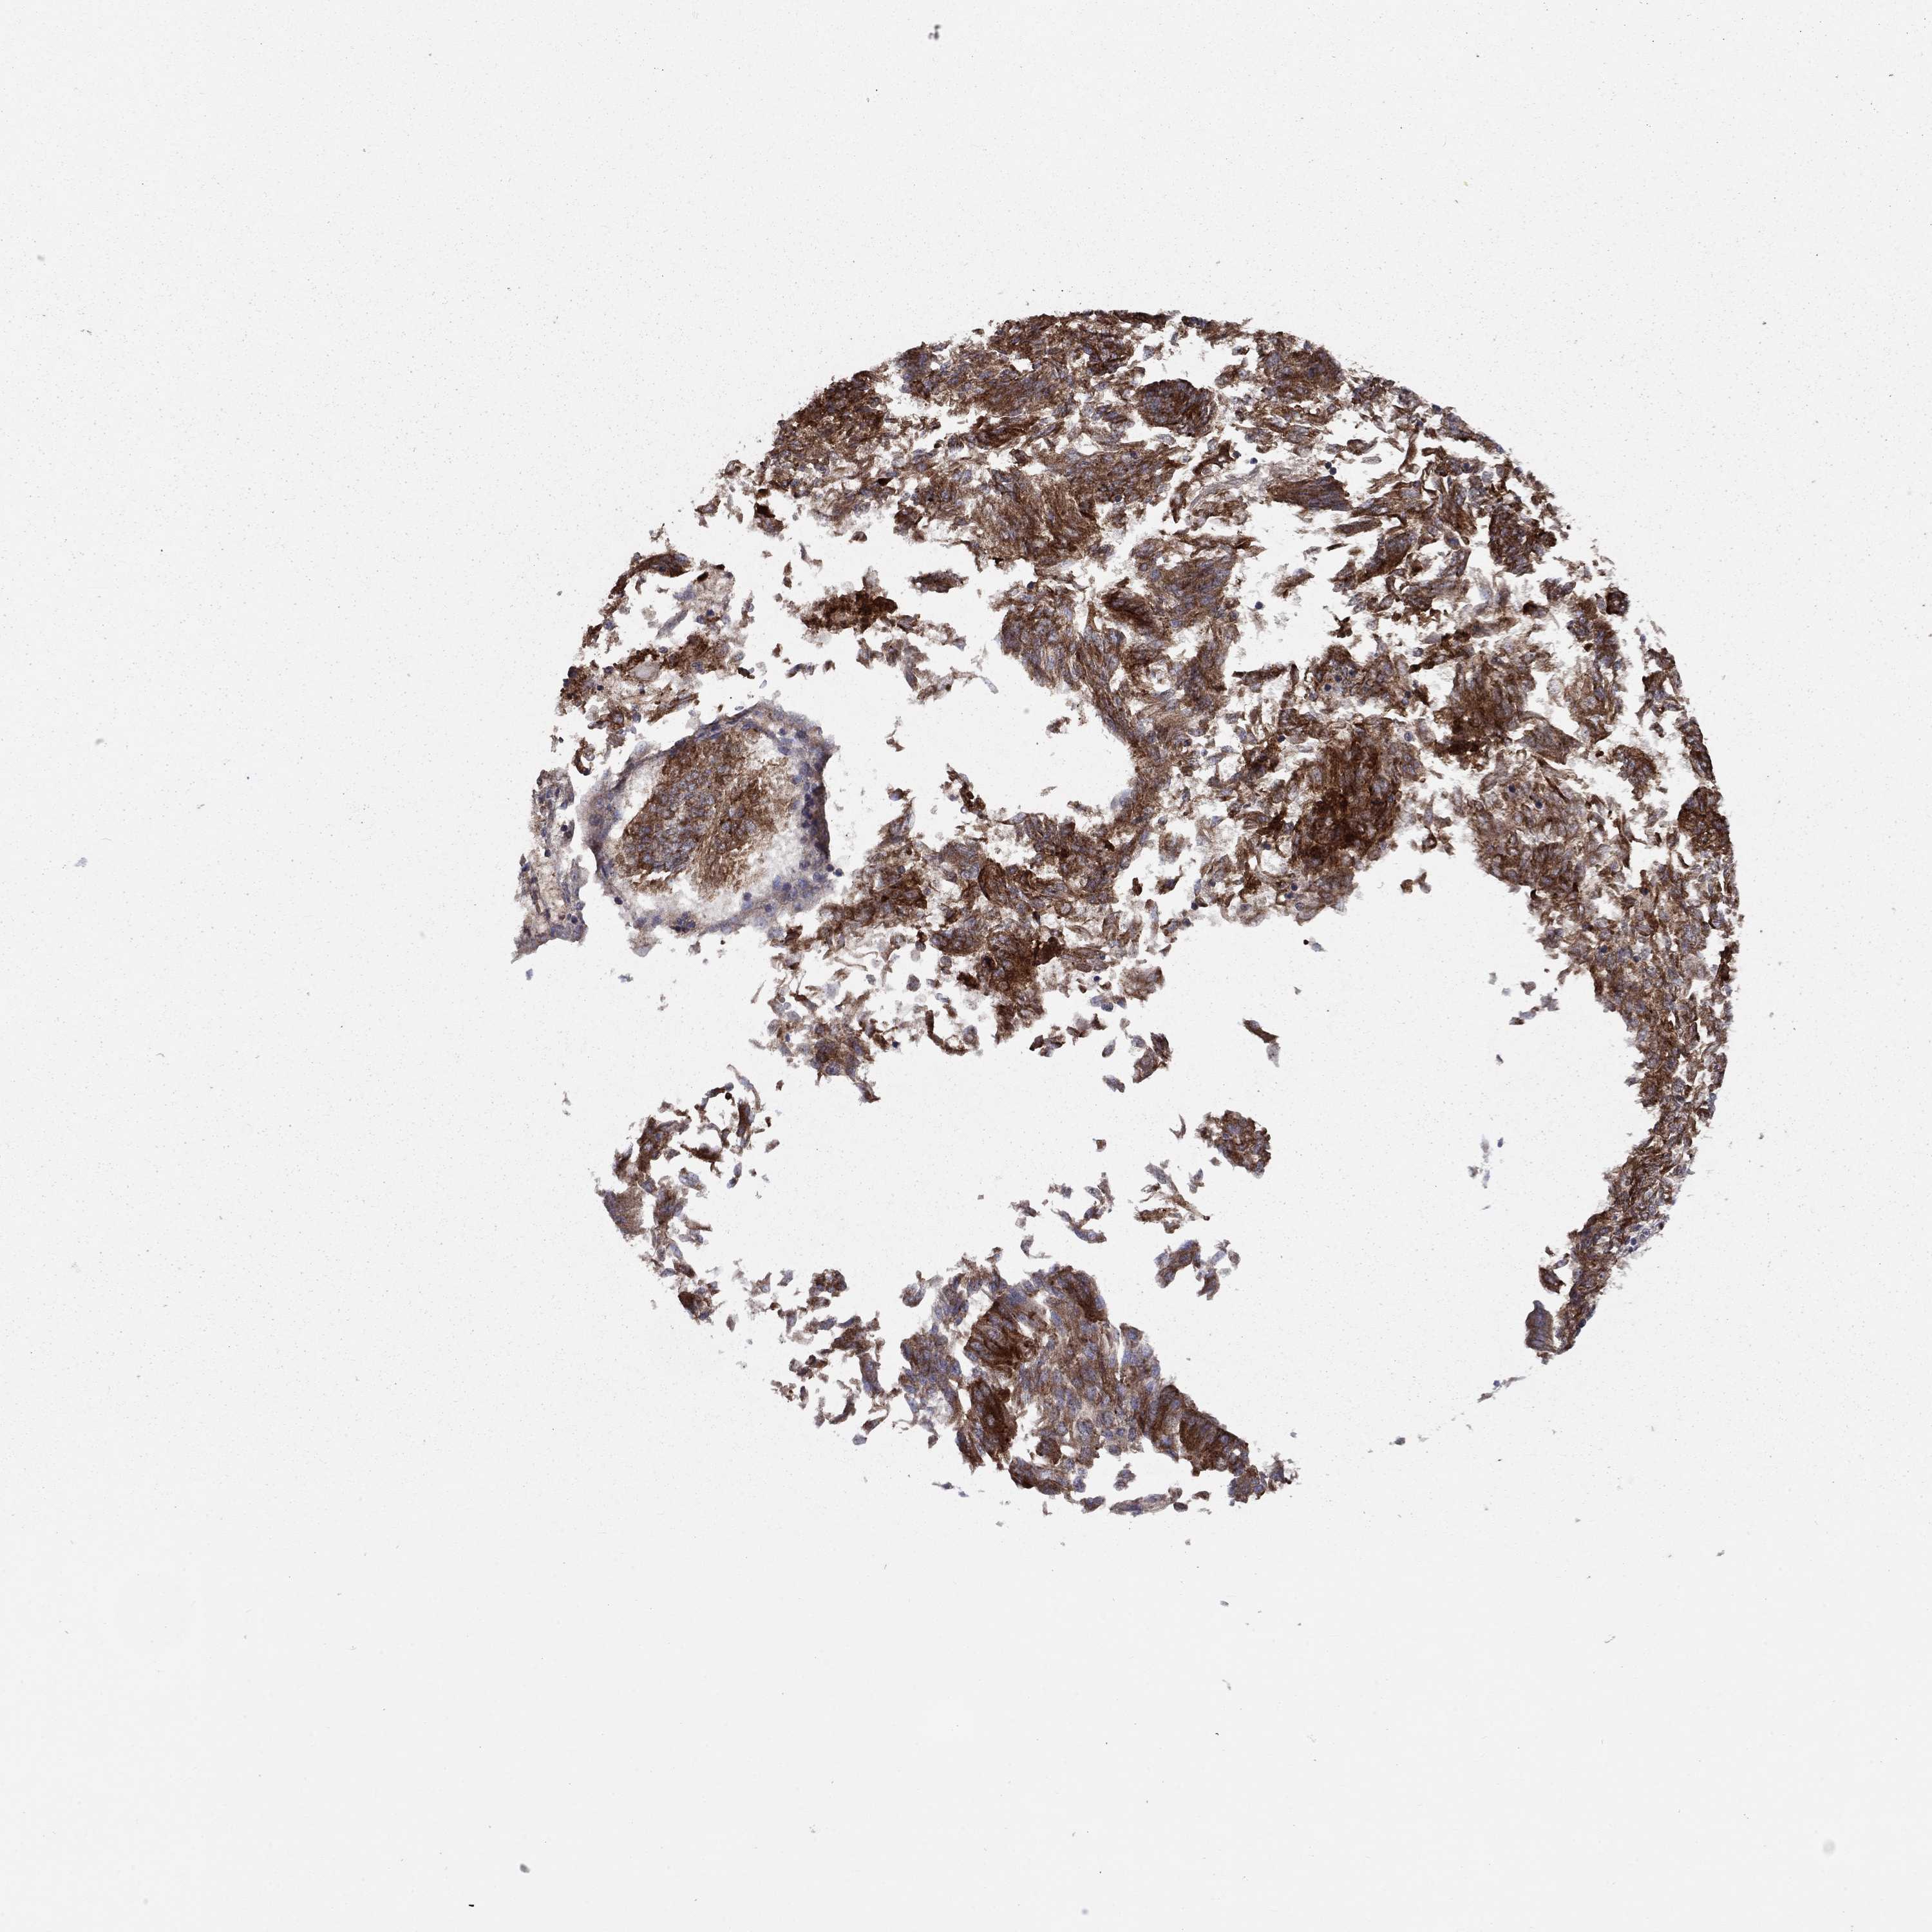

ENDOMETRIAL CANCER - Protein expressioni

A mouse-over function shows sample information and annotation data. Click on an image to view it in a full screen mode. Samples can be filtered based on level of antibody staining by selecting one or several of the following categories: high, medium, low and not detected. The assay and annotation is described here.

Note that samples used for immunohistochemistry by the Human Protein Atlas do not correspond to samples in the TCGA dataset.

Antibody stainingi

Antibody staining in the annotated cell types in the current human tissue is reported as not detected, low, medium, or high, based on conventional immunohistochemistry profiling in selected tissues. This score is based on the combination of the staining intensity and fraction of stained cells.

Each image is clickable and will lead to virtual microscopy that enables deeper exploration of all samples and also displays staining intensity scores, fraction scores and subcellular localization as well as patient and tissue information for each sample.

Antibody HPA030933

Staining

High

Medium

Low

Not detected

Intensity

Strong

Moderate

Weak

Negative

Quantity

>75%

75%-25%

<25%

None

Location

Nuclear

Cytoplasmic/membranous

Cytoplasmic/membranous,nuclear

Adenocarcinoma, NOS